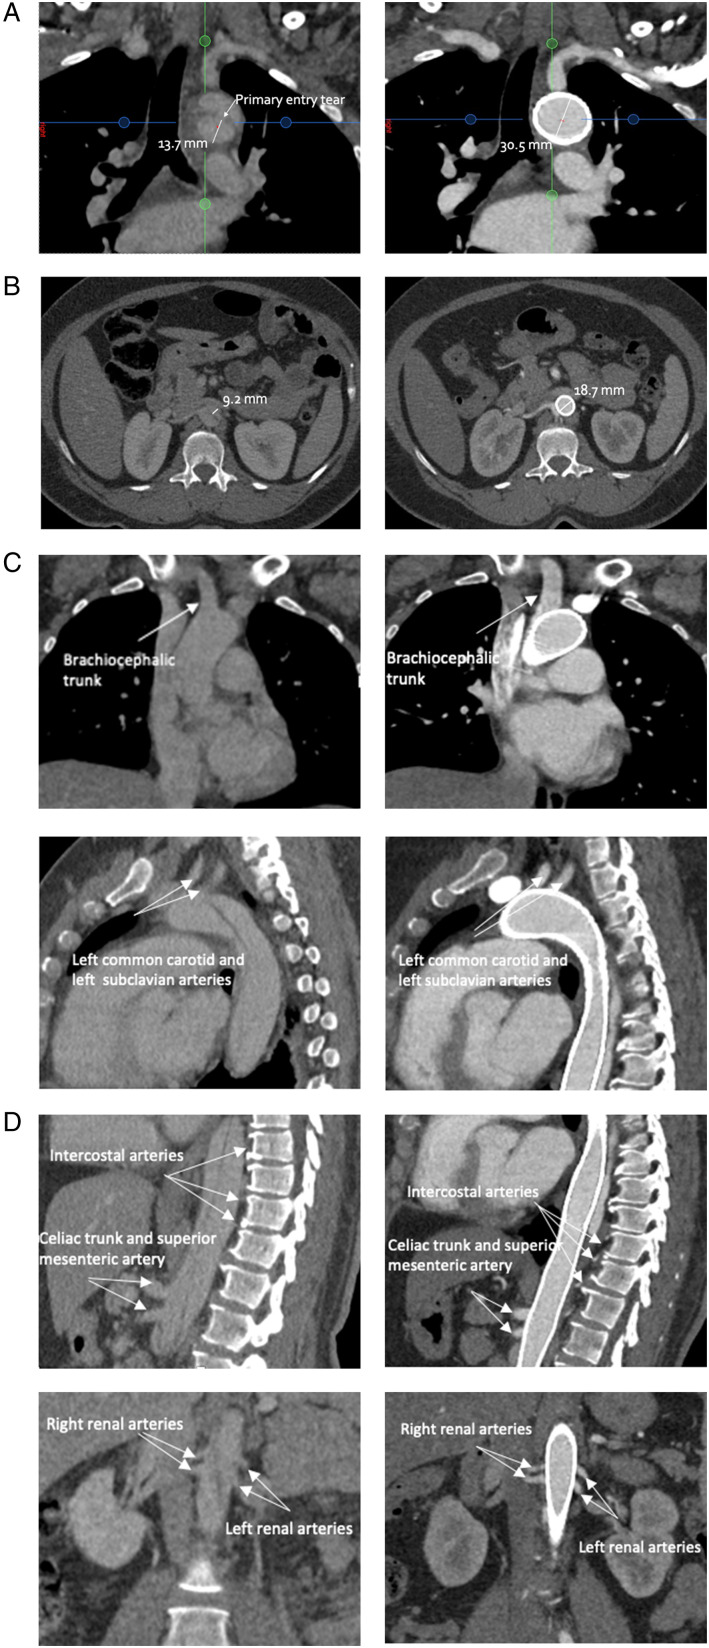

Case report: A 50-year-old female patient presented to the emergency department with an acute type B aortic dissection. Conservative medical treatment did control blood pressure but did not alleviate her dissection symptoms. She was treated endovascularly with multilayer stents extensively covering the whole dissected area. HThe aortic arch side branches, visceral arteries and renal arteries remained patent after treatment. The recovery was uneventful, and she was discharged the day after the intervention. At 6- and 12-month follow-up, the patient remained asymptomatic, the true lumen volume increased and all side branches remained patent.

Conclusion: We present a case of the use of a multilayer stent for acute type B aortic dissection. This technique allows to treat the whole dissection with low risk of paraplegia or side branch occlusion. Long-term results of ongoing clinical studies should confirm the place of the multilayer stent as a treatment option for type B aortic dissection.